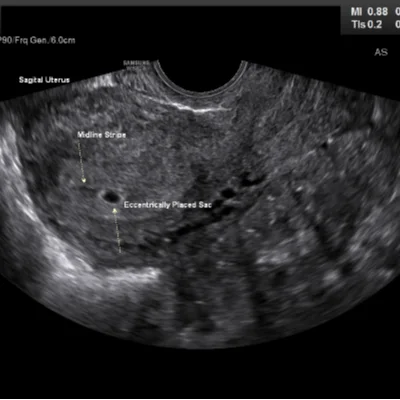

Early Pregnancy Scans

Confirm gestational age and fetal viability

Follicular Study

For individuals undergoing fertility treatment or natural cycle monitoring, follicular studies track ovarian follicle development. These scans help determine ovulation timing and guide assisted reproductive procedures.